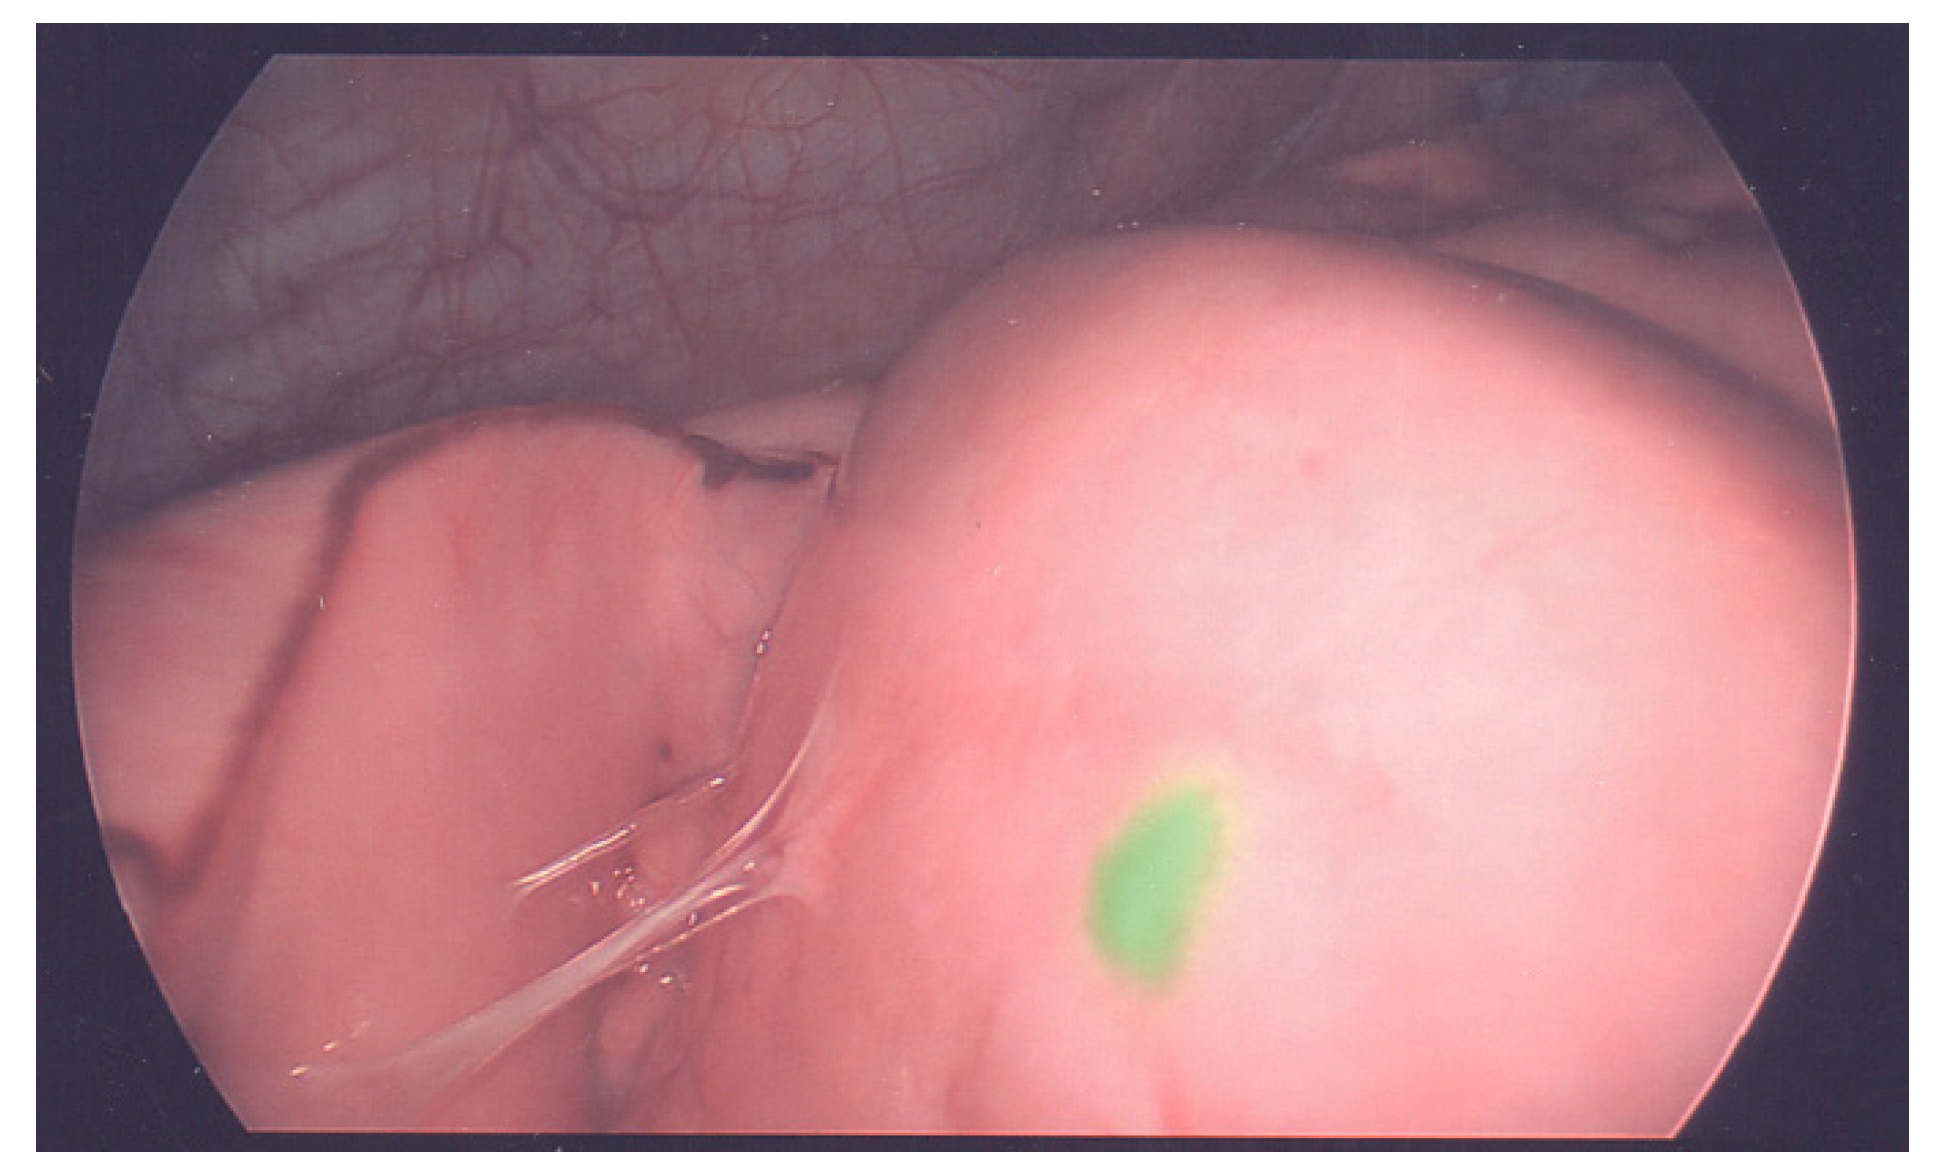

5. Advancement in Techniques to Make Tumors Resectable

6. Advances Intraoperative Techniques and Approaches to Local Control

- Souzaki, R.; Kawakubo, N.; Matsuura, T.; Yoshimaru, K.; Koga, Y.; Takemoto, J.; Shibui, Y.; Kohashi, K.; Hayashida, M.; Oda, Y.; et al. Navigation surgery using indocyanine green fluorescent imaging for hepatoblastoma patients. Pediatr. Surg. Int. 2019, 35, 551–557. [Google Scholar] [CrossRef] [PubMed]

- Yamada, Y.; Hoshino, K.; Mori, T.; Kawaida, M.; Abe, K.; Takahashi, N.; Fujimura, T.; Kameyama, K.; Kuroda, T. Metastasectomy of Hepatoblastoma Utilizing a Novel Overlay Fluorescence Imaging System. J. Laparoendosc. Adv. Surg. Tech. A 2018, 28, 1152–1155. [Google Scholar] [CrossRef]

- Yamamichi, T.; Oue, T.; Yonekura, T.; Owari, M.; Nakahata, K.; Umeda, S.; Nara, K.; Ueno, T.; Uehara, S.; Usui, N. Clinical application of indocyanine green (ICG) fluorescent imaging of hepatoblastoma. J. Pediatr. Surg. 2015, 50, 833–836. [Google Scholar] [CrossRef]

- Kitagawa, N.; Shinkai, M.; Mochizuki, K.; Usui, H.; Miyagi, H.; Nakamura, K.; Tanaka, M.; Tanaka, Y.; Kusano, M.; Ohtsubo, S. Navigation using indocyanine green fluorescence imaging for hepatoblastoma pulmonary metastases surgery. Pediatr. Surg. Int. 2015, 31, 407–411. [Google Scholar] [CrossRef]

- Takahashi, N.; Yamada, Y.; Hoshino, K.; Kawaida, M.; Mori, T.; Abe, K.; Fujimura, T.; Matsubara, K.; Hibi, T.; Shinoda, M.; et al. Living Donor Liver Re-Transplantation for Recurrent Hepatoblastoma in the Liver Graft following Complete Eradication of Peritoneal Metastases under Indocyanine Green Fluorescence Imaging. Cancers 2019, 11, 730. [Google Scholar] [CrossRef] [Green Version]